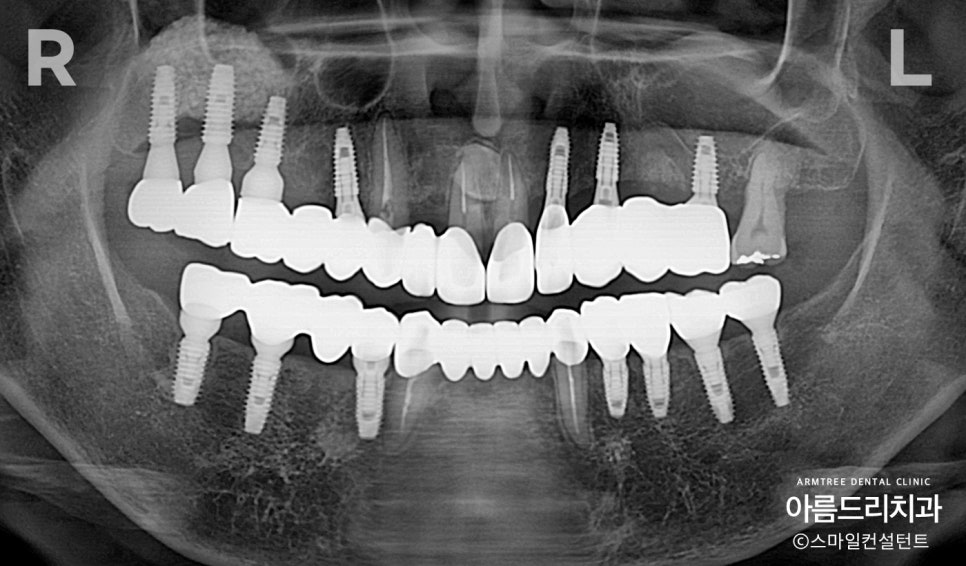

듬성 듬성 발치가 되어 있습니다. 빼면서 바로 임플란트를 심었다면 좋았을텐데 아쉽네요

발치하지 않은 남은 치아들도 상태가 좋지 않았고

어금니는 이미 여러개의 임플란트를 심었습니다.

그런데 오른쪽 어금니가 씹히질 않네요ㅠㅠ

발치하지 않은 치아부분 뼈가 많이 튀어나와 있습니다.(파란색선)

반대로 발치된 곳은 뼈가 푹 꺼져있네요. (노란색선)

앞니 2개가 툭~ 튀어나와 있습니다.

바로 옆치아가 발치됐고 뼈가 흡수돼서

상대적으로 더 튀어나와 보이네요.

오른쪽 위쪽과 아래쪽의

임플란트 위치를 잘못 계산한 결과입니다.

위에 맨 뒤 치아는 아래에 짝꿍이 없기

때문에 안 심어도 되는 상황입니다.

더군다나 위 아래 치아 맞물림을 맞춰놓지

않아 실제로 한 점만 씹히고 나머지 부분은

다 붕~ 떠 있는 상태였습니다.

밥이 잘 안 씹혔을텐데...,

환자분은 어태껏 잘 몰랐다고 하시네요.

앞니 각도가 많이 뻐드러져 있습니다.

어금니쪽은 교합(초록색)을 제대로

안 맞춰놔서 위 아래가 뜨는 게 보이는 상태!

앞니 각도를 줄여서 입이 들어가도록 했습니다.

어금니 교합을 맞춰서 밥이 잘 씹히도록 했으며,

얼굴 길이를 살짝 줄이고 앞니 각도를 조절해서

입술이 편하게 다물어지도록 치료 하였습니다.